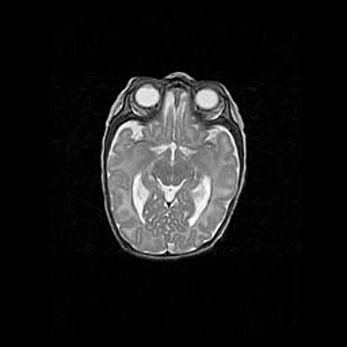

Церебральная ишемия II.

Возраст: 7 дней

Вес: 3350 г

Пол: женский

Окружность головы: 35 см

Срок гестации: 39 недель

Ишемия головного мозга – это состояние, которое развивается в ответ на кислородное голодание вследствие недостаточного мозгового кровообращения. У новорожденных она является следствием дефицита кислорода, что ведет к метаболическим расстройствам различной степени тяжести в тканях головного мозга, в том числе к развитию коагуляционных некрозов и гибели нейронов.